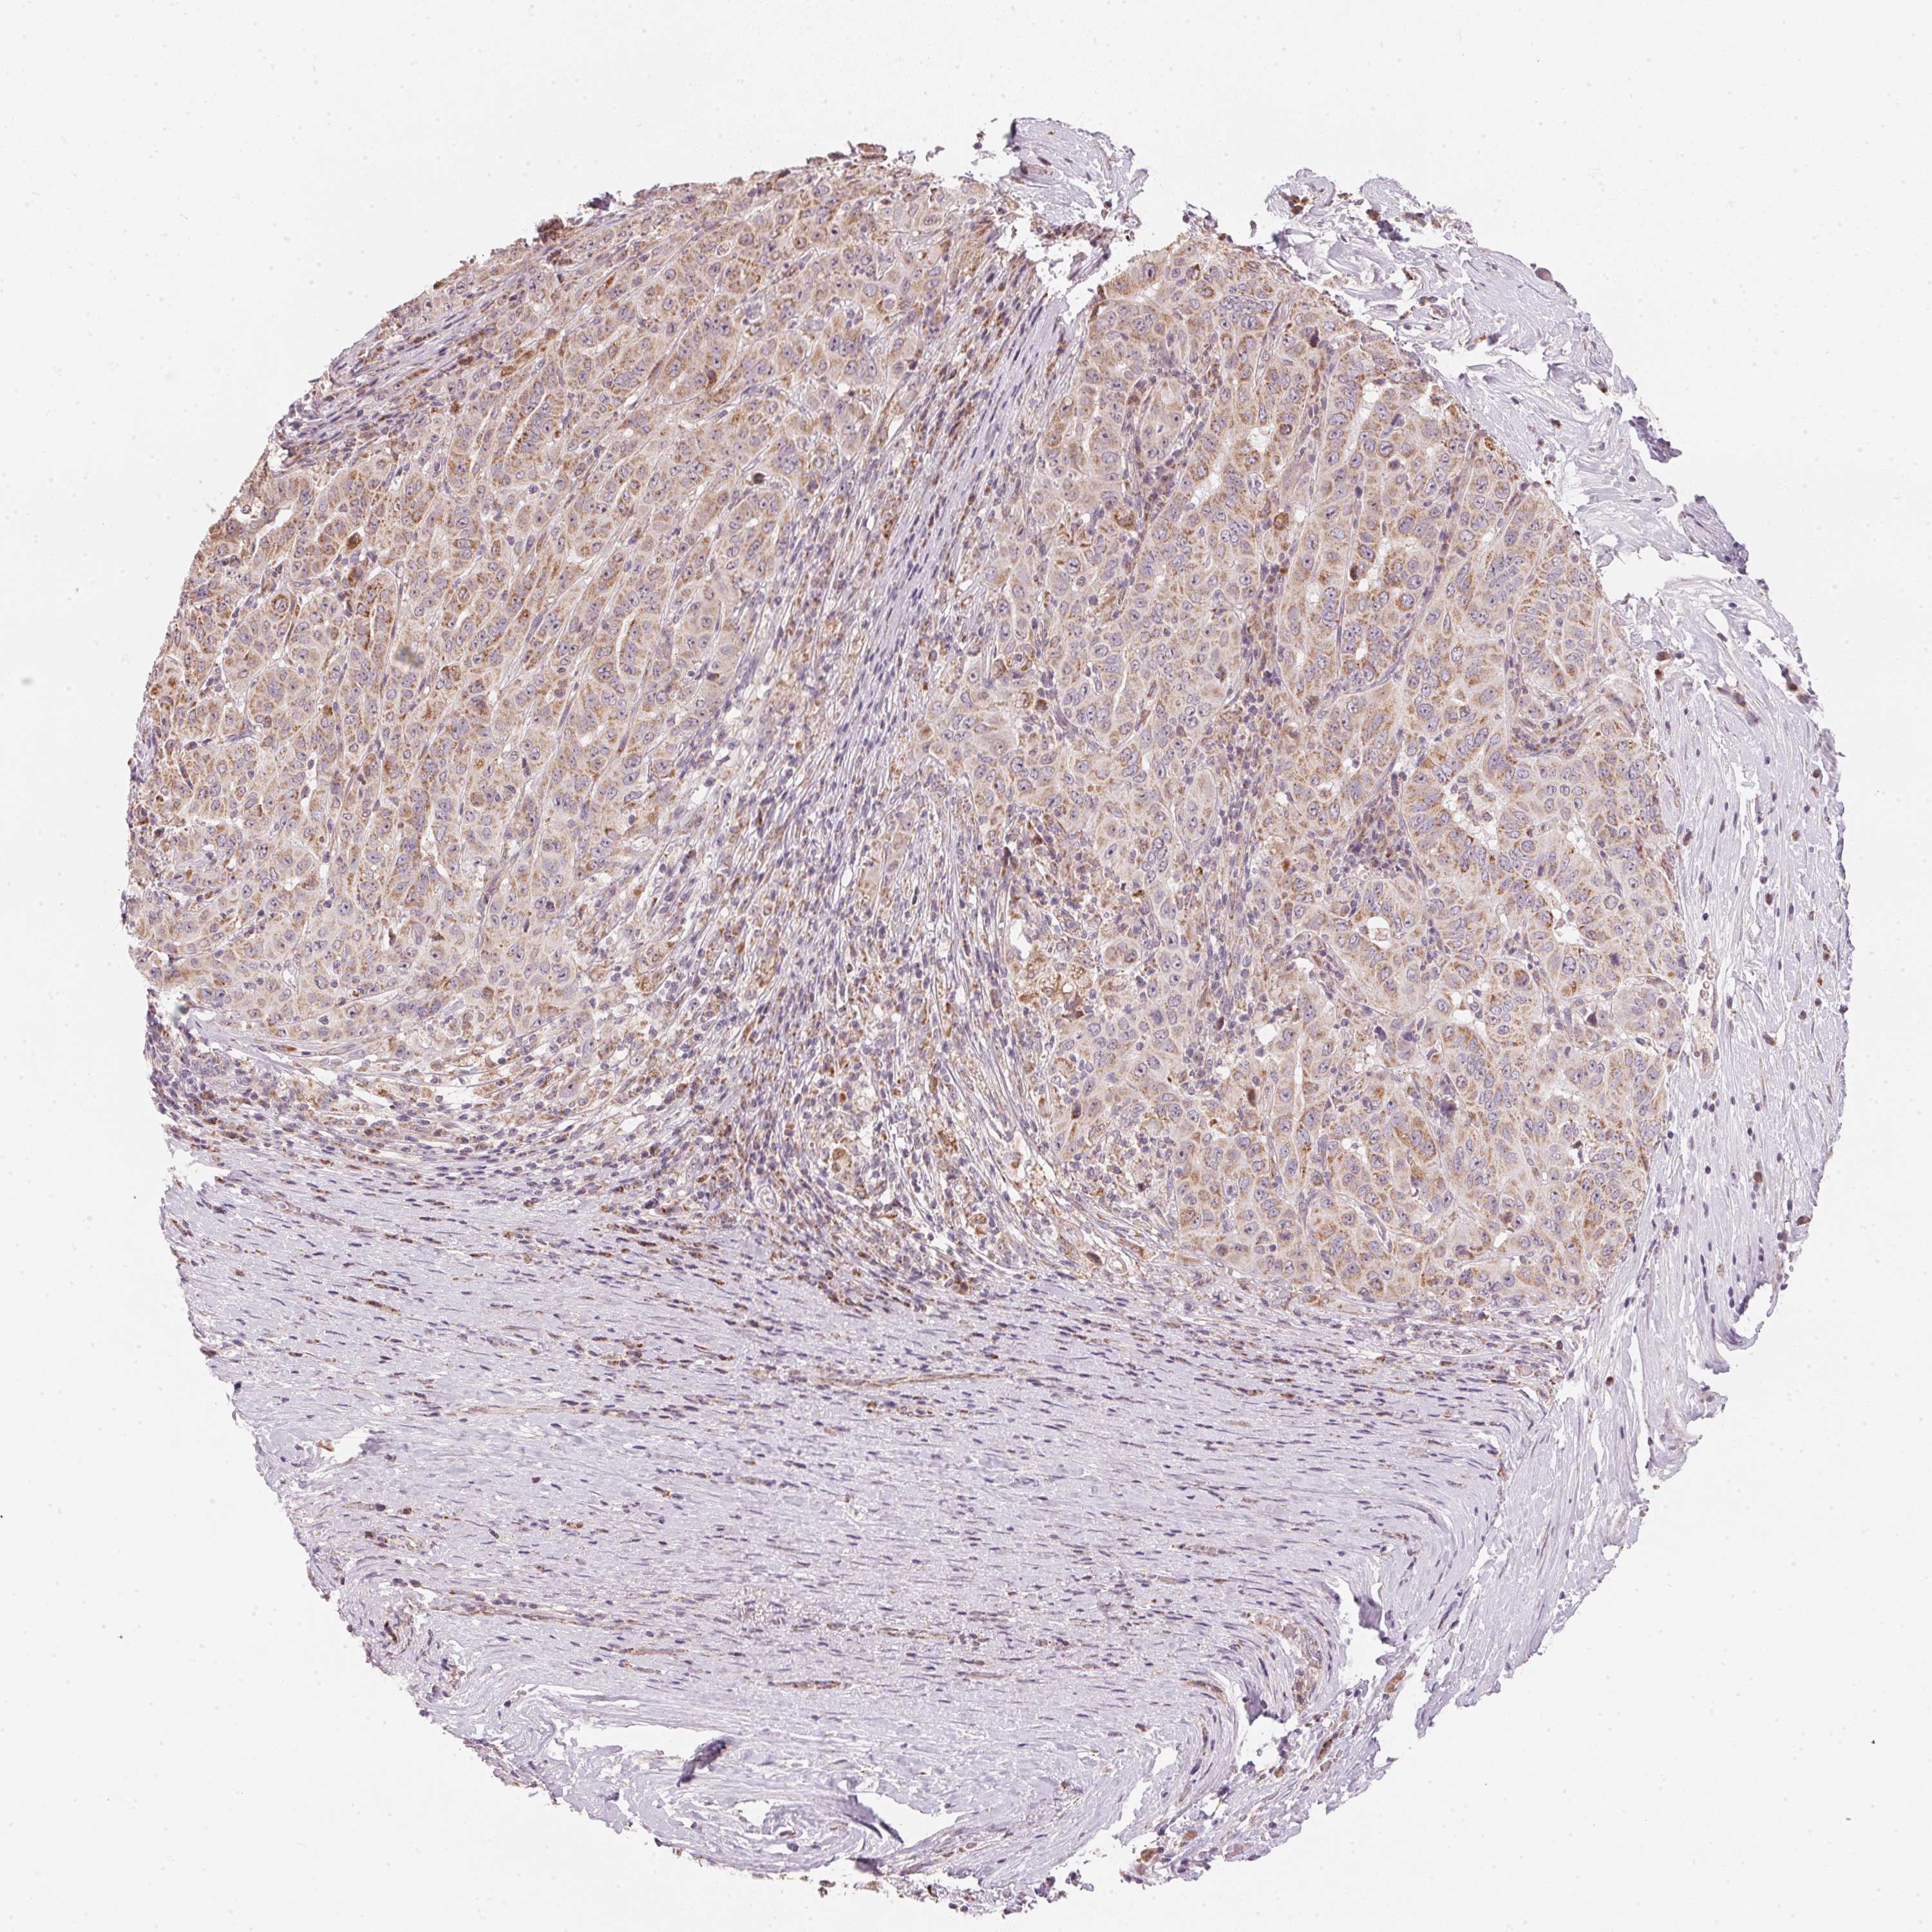

PANCREATIC CANCER - Protein expressioni

A mouse-over function shows sample information and annotation data. Click on an image to view it in a full screen mode. Samples can be filtered based on level of antibody staining by selecting one or several of the following categories: high, medium, low and not detected. The assay and annotation is described here.

Note that samples used for immunohistochemistry by the Human Protein Atlas do not correspond to samples in the TCGA dataset.

Antibody stainingi

Antibody staining in the annotated cell types in the current human tissue is reported as not detected, low, medium, or high, based on conventional immunohistochemistry profiling in selected tissues. This score is based on the combination of the staining intensity and fraction of stained cells.

Each image is clickable and will lead to virtual microscopy that enables deeper exploration of all samples and also displays staining intensity scores, fraction scores and subcellular localization as well as patient and tissue information for each sample.

Antibody HPA067252

Staining

High

Medium

Low

Not detected

Intensity

Strong

Moderate

Weak

Negative

Quantity

>75%

75%-25%

<25%

None

Location

Nuclear

Cytoplasmic/membranous

Cytoplasmic/membranous,nuclear

Adenocarcinoma, NOS